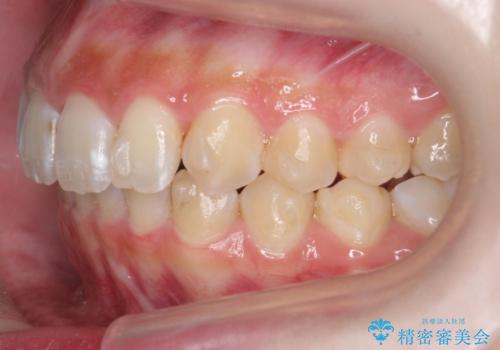

前歯の並び インビザライン 非抜歯で 深いかみ合わせの治療

- 前歯の並びを気にして来院。

上の前歯が内側に倒れこんでいました。

インビザラインで前歯の並びを整えています。

前歯の重なりが大きいいわゆる過蓋咬合を呈していましたが、ある程度適正な重なりにすることができました。